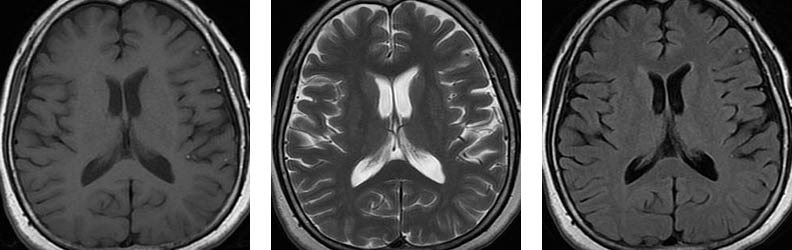

Üç farklı seviyeden aksiyal planda TlAG, T2AG ve FLAIR görüntüler Subaraknoid mesafelerde, özellikle BOS'un hipointens izlendiği TlAG ve FLAIR sekanslarda dağınık milimetrik hiperintens od aklar dikkati çekmektedir.

Pantopaque yağa benzer şekilde kısa T1 ve T2 reIaksasyon sürelerine sahiptir. Bu nedenle Tl ve T2AG'Ierde hiperintens olarak izIenirIer ve özellikle BOS mesafelerinin baskılandığı T1AG ve FLAIR sekanslarında dikkati çekerler.